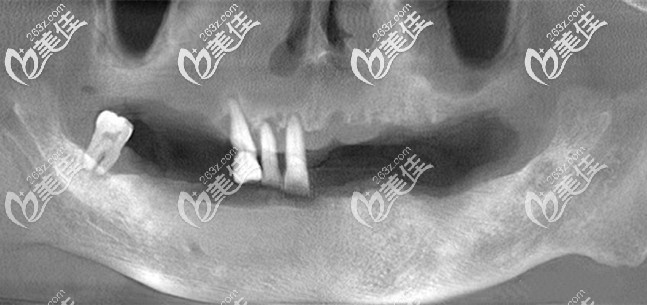

为我面诊的是孙医生,根据CT片的结果来看,牙槽骨吸收比较厉害,仅有的四颗牙齿已经能看到牙根,建议拔除后直接做全口种植牙。

目前较为先进的种植技术则是即刻种植技术,而我的骨量也符合做全口即刻种植牙,为了缩短治疗时间,降低成本,医生建议我选择allon4/6全口种植牙。

由于我的骨量还算可以,所以选择了更加稳固的半口6颗种植牙,自然价格也要比半口4颗要贵呀,全口种植牙花了我14万元,用的是常见的登腾(Dentium)种植体。